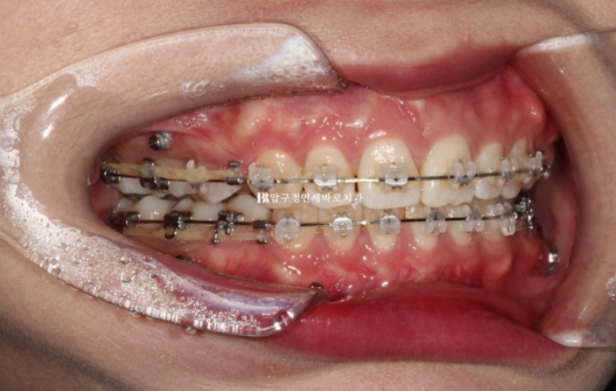

24.03

치료시작 1년 1개월째 사진입니다.

발치공간은 모두 없어졌고 미니스크류를 이용하여 중심선을 맞추고 있습니다.

마무리 과정이라고 부르는 단계입니다.